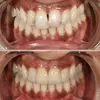

Zirconium Applications

Porcelain Applications

Laminate Veneer